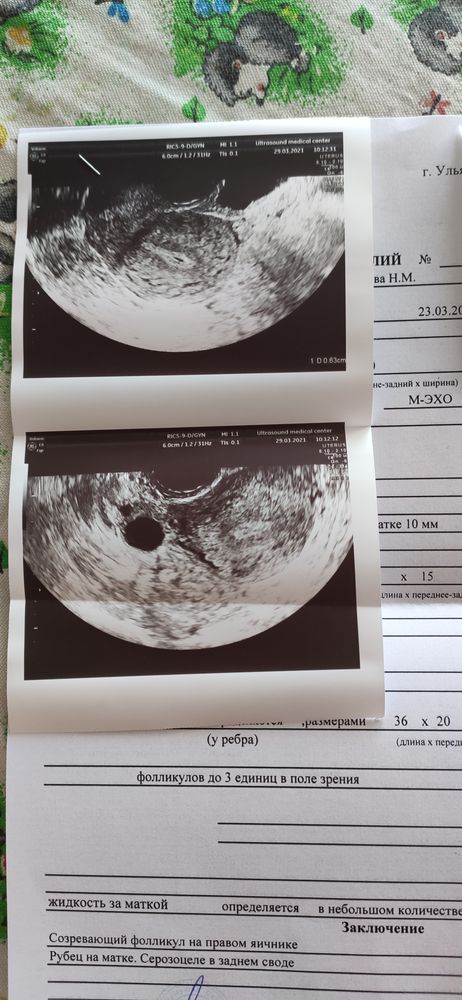

утрожестан месячные пришли раньше Обновлено: 01 .02 .2022 ЛЕНА Балобанова 02 .08 .2020 Новороссийск По традиции По традиции , забираю ваши месячные )отдавайте, буду за всех отдуваться ) 🤗🥵пришли на неделю раньше, думаю потому что утрожестан вставляла, как раз на 10 день приема пришли, ночью жуткие боли были, пила кетанов и спазмалгон .

Не помогало . Недавно врач назначила Утрожестан на 11-й день цикла(12 июня) и приём препарата должен был закончится 25 июня - это один цикл, всего 6 . Месячные пришли сегодня, 19 июня, тёмные и скудные .

Здравствуйте, была задержка месячных более 20 дней, гинеколог назначила утрожестан, 5 дней два раза в день по 100 мл, месячные начались в последний день приема, это нормально, что они так быстро пришли и если бы была . . .